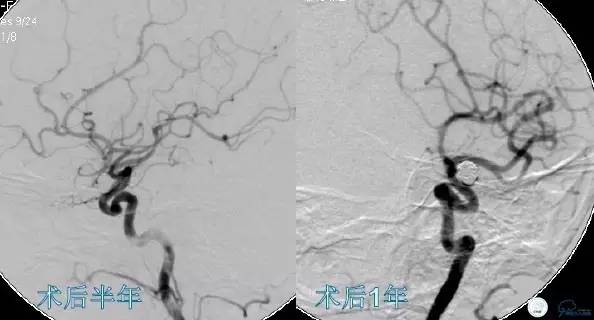

Case3 左ICA床突旁动脉瘤术后复发

影像随访:术后6个月第一次复查造影,如果随访结果稳定,1~2年再复查一次。

复发

★2010年以前:复发率是7.6%~31.6%;

★2010年以后:复发率是5~30%;

★大多数研究认为6个月的复查对于发现动脉瘤复发是不够的,多建议每年一次复查;

★可能与该段动脉瘤的形态学特征和血流动力学因素有关。